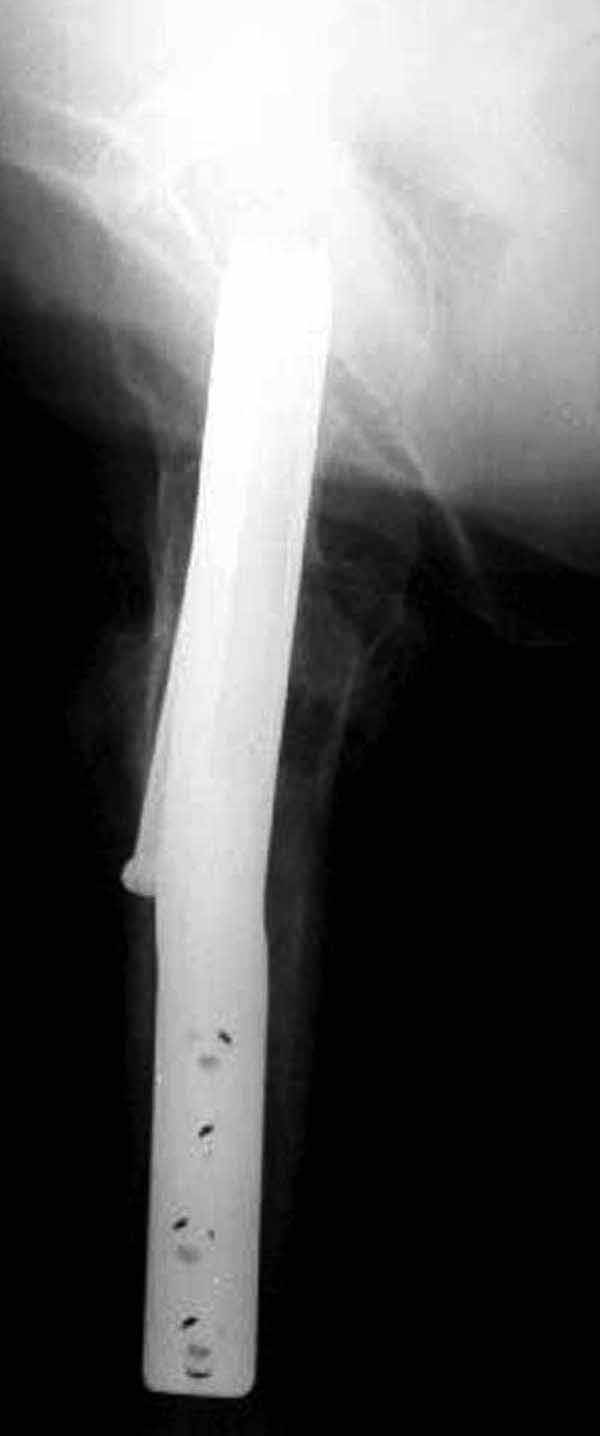

Пациентка Ш. 76 лет, 11 дней назад прооперирована по поводу вколоченного субкапитального перелома шейки левой бедренной кости, 3-мя канюлированными винтами. Вчера пациентка упала в палате. И вот результат- подимплантатный подвертельный перелом левой бедренной кости. Уважаемые коллеги, пожалуйста посоветуйте какой метод дальнейшего лечения предпринять дальше.Соматически пациента повышенного питания, страдает варикозной болезнью нижних конечностей.Из предложенных вариантов коллег - целллокастовая укороченная кокситная повязка, скелетное вытяжение сроком на 40-45 суток - отпали сразу, так как необходимо активизация пациентки.На данный момент рассматриваем следующие варианта реостеосинтеза:(наличие технических возможностей) 1. Длинная Gamma 3 Stryker (с предварительной интраоперационной фиксацией головки спицами).2. Трохантерный штифт DePuy с 2-мя метафизарными винтами в проксимальном отделе, (также с интраоперационной фиксацией головки спицами. Очень настораживает стабильность фиксации с проксимальном отделе с связи с выборкой костной ткани ранее находящимися там канюлированными винтами. Сейчас пациентка находится на скелетном вытяжении, с дисциплинирующим грузом. Операция планируется после праздников. Заранее извиняемся за качество и неполное соответствие проекций на R-ммах (R-служба отдельная песня). При интраоперационном ЭОП-контроле винты в аксиальной проекции разнесены по шейке.

два в нижней части шейки. Более стабильная структура как раз обратная: два шурупа в проксимальной части шейки , и не дальше центральной части головки, иначе есть риск пенетрации. дистальный винт мог бы быть выше уровня малого вертела. Его дистальное расположение описано с увеличенным риском послеоперационного перелома.

Согласен с Николаем, винты распоожены так, чтобы эту "мину" заложить. И два внизу, и не должны, даже если один он там, они входить ниже уровня малого вертела, это резко повышает риск подвертельного перелома. Что до остеосинтеза - учитывая 76 лет, более подходящей представляется большего диаметра винт в шейке, то есть гамма.

Работа Burstein AH and Wright TM: Fundamentals of Orthopaedic Biomechanics. Williams & Wilkins, Baltimore, pp. 160-169, 1994 доказывает, что шурупы, введенные на уровне малого вертела или ниже, приводят к осложнению. Введенные шурупы под 135 и больше градусов в 20% осложнились подвертельными переломами бедра.

У больных с ожирением и соматическими заболеваниями нежелательно открывать место перелома. Гвозди от DePuy с двумя шурупами рассчитаны для переломов бедра, и приходилось их применить для фиксации подвертельных переломов, но более адекватную фиксацию создает Gamma 3.